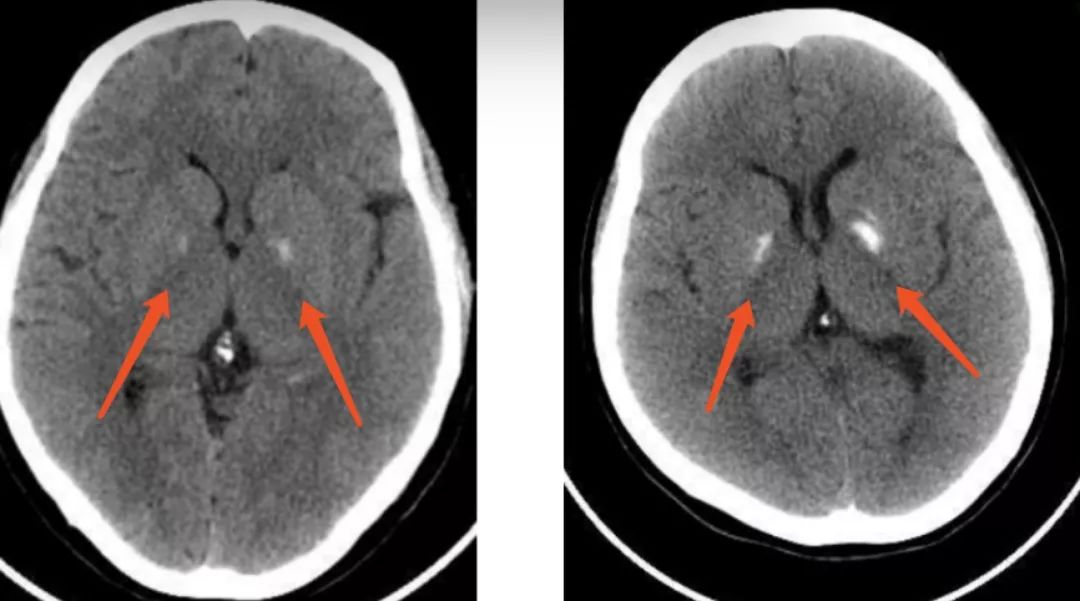

脑袋里的这么多瘤瘤竟然跟心脏有关(⊙o⊙)_手机搜狐网